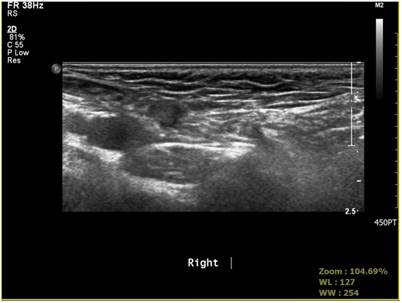

Fig 4

Positive sonographic finding of processus vaginalis.

The accuracy of sonography from well-known studies was of a similar figure to the accuracy of 64.5% resulted in our study. The accuracy of sonography can be affected by ultrasound resolution, diagnostic criteria, and skillfulness of the operator. In our study, sonography was performed by one genitourinary radiologist. The measurement of the inner ring size was not performed on PPV. We set abnormal shading on sonography as a positive finding. By comparing sonography results with findings of laparoscopy, we were able to better understand the sonographic accuracy of contralateral PPV (Fig. 4, Fig. 5).

The accuracy of sonography in our study was 64.5%. In our study, 35 out of 95 patients without abnormal findings in the preoperative sonography showed positive PPV. The preoperative sonography had higher false negative rate base on laparoscopic finding for sensitivity. The higher PPV rate in our study than previously reported PPV rate might be due to the sensitivity of laparoscopic examination. Broad multicenter study with more enrolled patients might lead to higher accuracy of preoperative sonography. Also, large scale studies with long-term follow-up are needed to determine the exact incidence of metachronous hernia in pediatric inguinal hernia patients. Expansion of laparoscopic surgery for pediatric inguinal hernia suggests that pediatric surgeons should do long-term follow-up of patients. We also need more studies on natural history of PPV because preoperative sonography alone is insufficient to confirm the status of PPV (Fig. 6, Fig. 7).